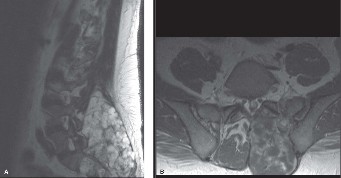

Understand the risks and benefits of cement augmentation for osteoporotic compression fractures? CASE 9 A 46-year-old male presents with a 1-year history of worsening low back and left leg pain. Despite having been treated for sciatica with physical therapy and manipulation, his symptoms are worse. He denies lower extremity weakness and bowel and bladder dysfunction. He does report increasing night pain and weight loss. On physical examination he has no deficits, but has a palpable, firm, fixed, nontender mass at the lumbosacral junction on the left. He presents with the following imaging studies, CT and MRI (Figs. 1–16 and 1–17).

Figure 1–16_Sagittal CT image through lumbar spine (A), Axial CT image through the lumbosacral junction (B).

Figure 1–17_Sagittal T2 weighted MRI of lumbar spine (A), axial T1-weighted image post-contrast of lumbar spine (B).

The best answer is (C). This is most likely a malignant process given his age, weight loss, presence of night pain, as well as the imaging characteristics. Workup for a bone lesion should include local and remote imaging, as well as laboratory work, including complete blood count, chemistry, and alkaline phosphatase. In certain circumstances, serum protein immunoelectrophoresis, prostate specific antigen, and carcinoembryonic antigen may be appropriate.

_Figure 1–18_Cartilaginous neoplasm invading through bone into marrow space (A), Highlights bone destruction and abnormal cellularity and atypia within the cartilage tumor (B), Tumor cells exhibit clear atypia (large, middle cell) and occasional binucleate forms (C). Images taken by David M. Meredith MD, Brigham & Women’s Hospital, Department of Pathology.

The best answer is (D). The slides show grade I chondrosarcoma. There is cellular tumor cartilage infiltrating the normal osteoid. Seen are plump nuclei with more than one cell per lacunae.